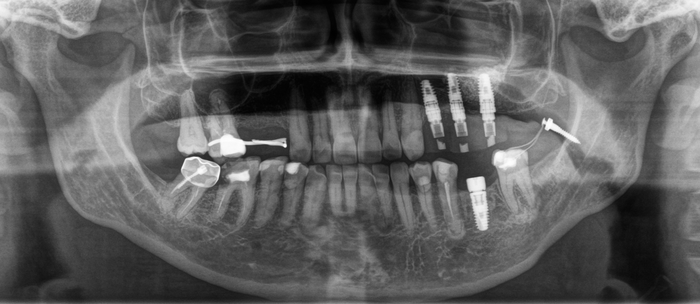

Вот результат после установки временной коронки и удаления минивинта:

Временные коронки делаются из фрезерованной пластмассы, поэтому не рентгеноконтрастны, хотя, если посмотреть внимательно, то можно увидеть неявные очертания коронок.

Бонусом еще небольшой клинический случай, как можно передвигать зубы на свое место:

Был установлен имплантат, и параллельно начато лечение у ортодонта. Как мы видим, нижний правый седьмой зуб наклонен, а верхний правый шестой несколько выдвинулся в сторону отсутствующего шестого на нижней челюсти.

Обратите внимание: необязательно устанавливать полноценную брекет-систему для того, чтобы устранить эту проблему. Достаточно приклеить 3 брекета на 4-й, 5-й и 7-ой зубы. Затем при помощи специальной пружины толкать проблемный зуб на свое место. На верхней челюсти ситуация несколько иная. Для устранения проблемы устанавливаются два ортодонтических винта: один со стороны щеки, а второй со стороны неба. К зубам клеятся две кнопки, и дается тяга.

И под другим углом: